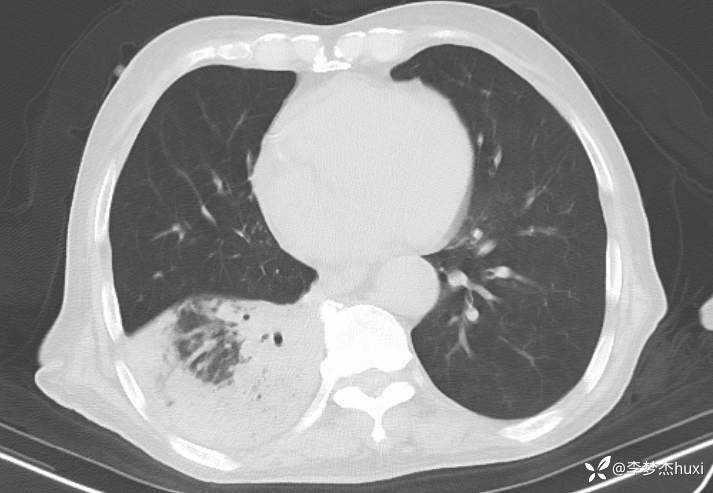

【现病史及既往史】: 1.患者老年 男,患者缘于3小时前无诱因出现意识不清,伴咳嗽、咳痰,痰不易咳出,伴发热,最高体温不详,院外应用“退热药物”(具体不详)治疗,无恶心、呕吐,无大小便失禁,无胸痛,今为求进一步治疗来院就诊,急诊查胸部及头CT:双侧基底节区腔隙性脑梗塞,脑白质稀疏,脑萎缩,脑干密度不均匀,右肺感染首为考虑,占位待除外,建议治疗后复查,右肺中叶局限性炎症,双肺间质性改变,主动脉及冠状动脉钙化,双肺气肿,左肺实性结节,建议复查,纵隔内及右肺门结节,右肺门增大。右肺下叶部分支气管堵塞。右侧胸膜局部增厚并少量积液,甲状腺密度不均匀,胆囊结石,右肾类圆形囊性密度影,建议结合超声。查血常规:白细胞数目 13.91*109/L,BNP前体 1360pg/ml。D-二聚体 0.8pg/ml。以“肺炎”收住院;。

4.辅助检查:急诊查胸部及头CT:双侧基底节区腔隙性脑梗塞,脑白质稀疏,脑萎缩,脑干密度不均匀,右肺感染首为考虑,占位待除外,建议治疗后复查,右肺中叶局限性炎症,双肺间质性改变,主动脉及冠状动脉钙化,双肺气肿,左肺实性结节,建议复查,纵隔内及右肺门结节,右肺门增大。右肺下叶部分支气管堵塞。右侧胸膜局部增厚并少量积液,甲状腺密度不均匀,胆囊结石,右肾类圆形囊性密度影,建议结合超声。查血常规:白细胞数目 13.91*109/L,BNP前体 1360pg/ml。D-二聚体 0.8pg/ml。。